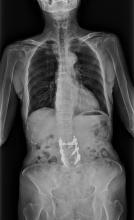

A randomized clinical trial of targeted, high-dose radiation for men with oligometastatic prostate cancer has shown the treatment to be an effective and safe option for patients who wish to delay hormone-suppression therapy. The phase II trial found that radiation therapy can generate an immune system response not previously believed possible in this type of cancer. Findings were presented at the 61st Annual Meeting of the American Society for Radiation Oncology (ASTRO), Sept. 15-18, 2019, in Chicago.